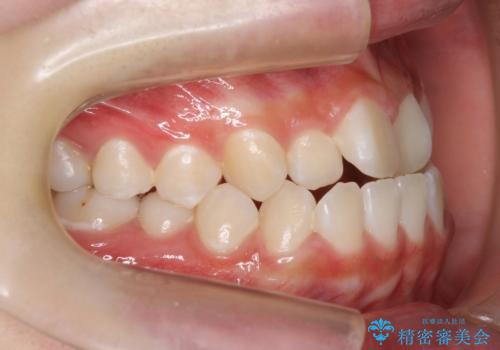

- 高校生で来院。受け口が主訴でした。

下の小臼歯を抜歯しましたが、その代わり下の親知らずを残して咬ませたので、歯の数は変わっていません。

ただし、左下の親知らずを残すには厚みのある歯ぐきを処置しています。(ディスタルウェッジ)

親知らずが歯ぐきに埋まっていると不潔になり、炎症を繰り返すため残しておくことが難しい場合が多いです。

今回は左下の小臼歯を1本抜歯してるのと、手術を行なって親知らずを顎に収めることができました。